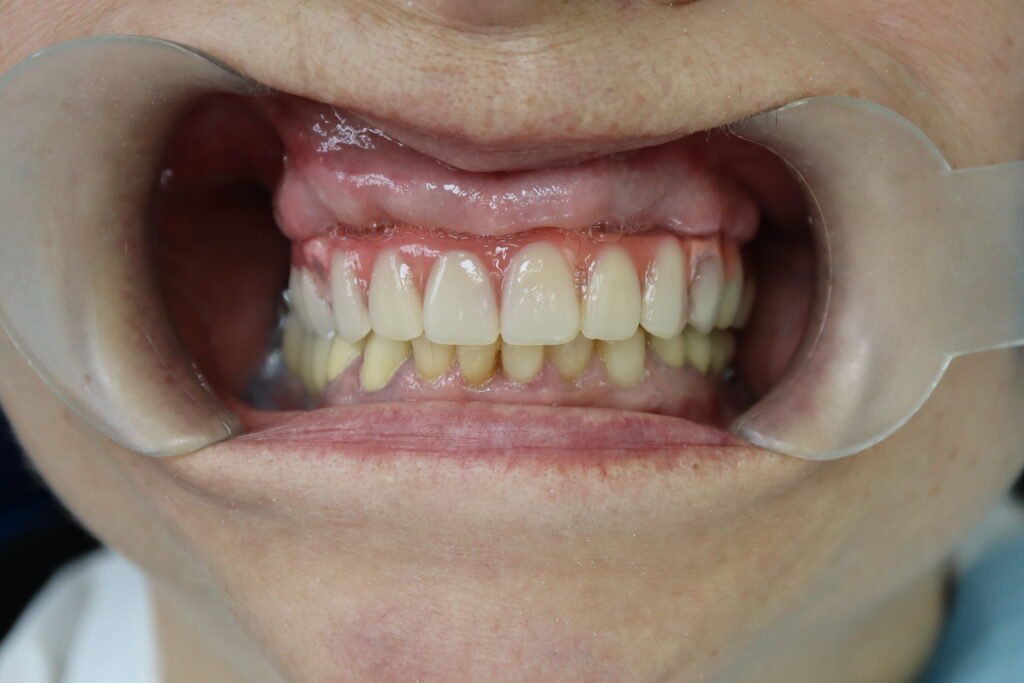

Ситуация до лечения

пациент до имплантации